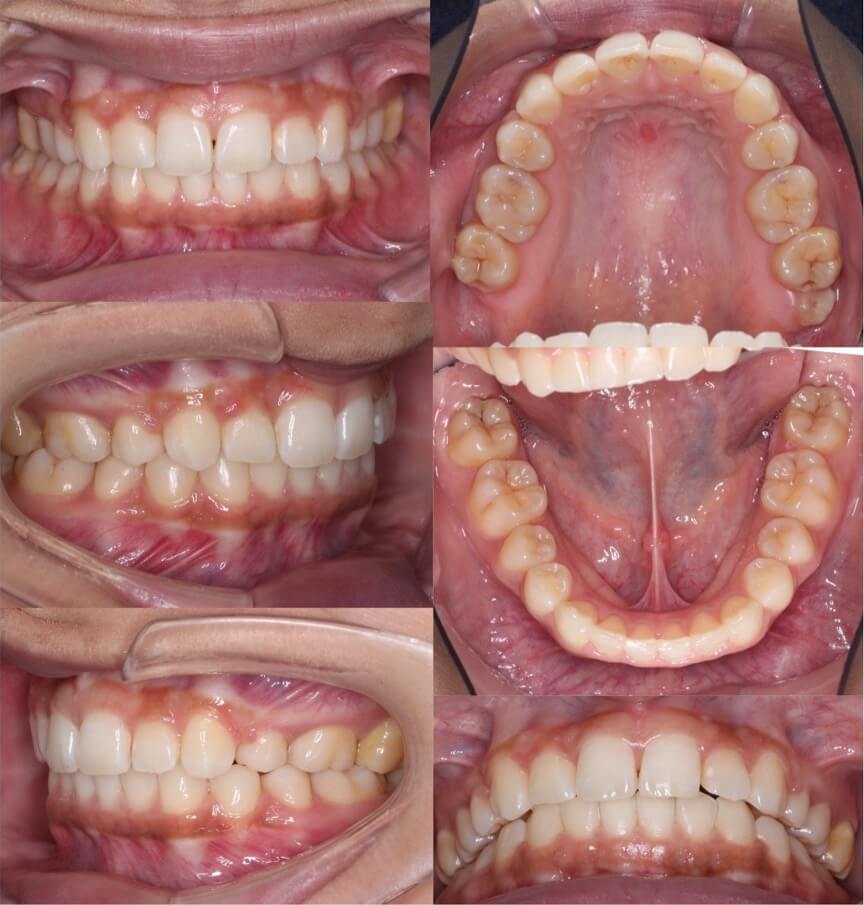

20代女性・マウスピース型装置

過蓋咬合の改善は見た目の変化は少ないのですが、口の中の歯並びの変化は大きいです。下の歯並びが見えるようになり正しいかみ合わせになりました。

<症例概要>

主訴:前歯のかみ合わせが悪い

年齢・性別:大学生女性

住まい:千葉県佐倉市

症状:過蓋咬合・右5番シザーズバイト・下顎叢生

治療方針:下顎前歯唇側傾斜による圧下

治療装置:マウスピース型矯正装置(アライナー装置)

アライナー枚数:43+27

治療期間:1年4か月

リテーナー:上下クリアタイプ

治療費用:990,000(税込)

代表的副作用:痛み・治療後の後戻り・歯根吸収・歯髄壊死・歯肉退縮

▶︎その他の副作用

【治療シミュレーション】

主に下の歯並びを前方に倒しながら歯茎方向に沈め(圧下)させ、過蓋咬合を改善していきます。